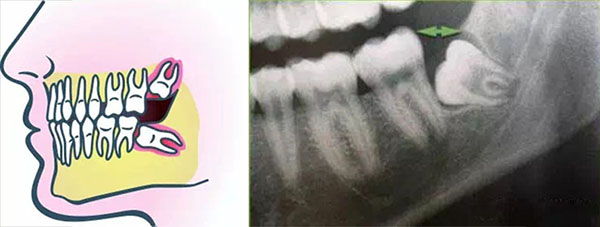

(4)智齿近中倾斜。近中倾斜的智齿可能会造成食物嵌塞。也有一些情况下智齿生长导致其直接顶在第二磨牙的根上。这种情况下建议尽早拔除,临床上经常遇到智齿将第二磨牙顶坏而需要同时将两颗牙拔除的情况,一旦发生这种情况,那就比较可惜了。。。